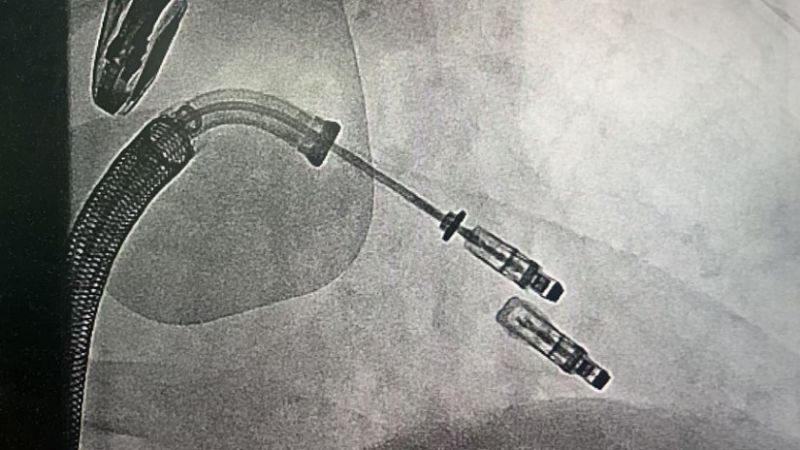

手術(shù)于11月4日下午進(jìn)行,通過股靜脈穿刺送入夾合器,在食道超聲實(shí)時(shí)引導(dǎo)下,精準(zhǔn)植入2枚瓣膜夾修復(fù)二尖瓣。整個(gè)過程歷時(shí)約2小時(shí),術(shù)中出血量僅50ml。術(shù)后次日,患者即可下床活動(dòng),復(fù)查顯示EF提升至46%,二尖瓣返流面積縮小至3.0cm2,左心房縮小至66mm,胸悶、氣短癥狀明顯緩解。

1.微創(chuàng)路徑:經(jīng)股靜脈穿刺,無需開胸或體外循環(huán);

2.精準(zhǔn)定位:在食道超聲和X線引導(dǎo)下,將夾合器送達(dá)二尖瓣位置,通過夾合病變瓣膜減少返流;